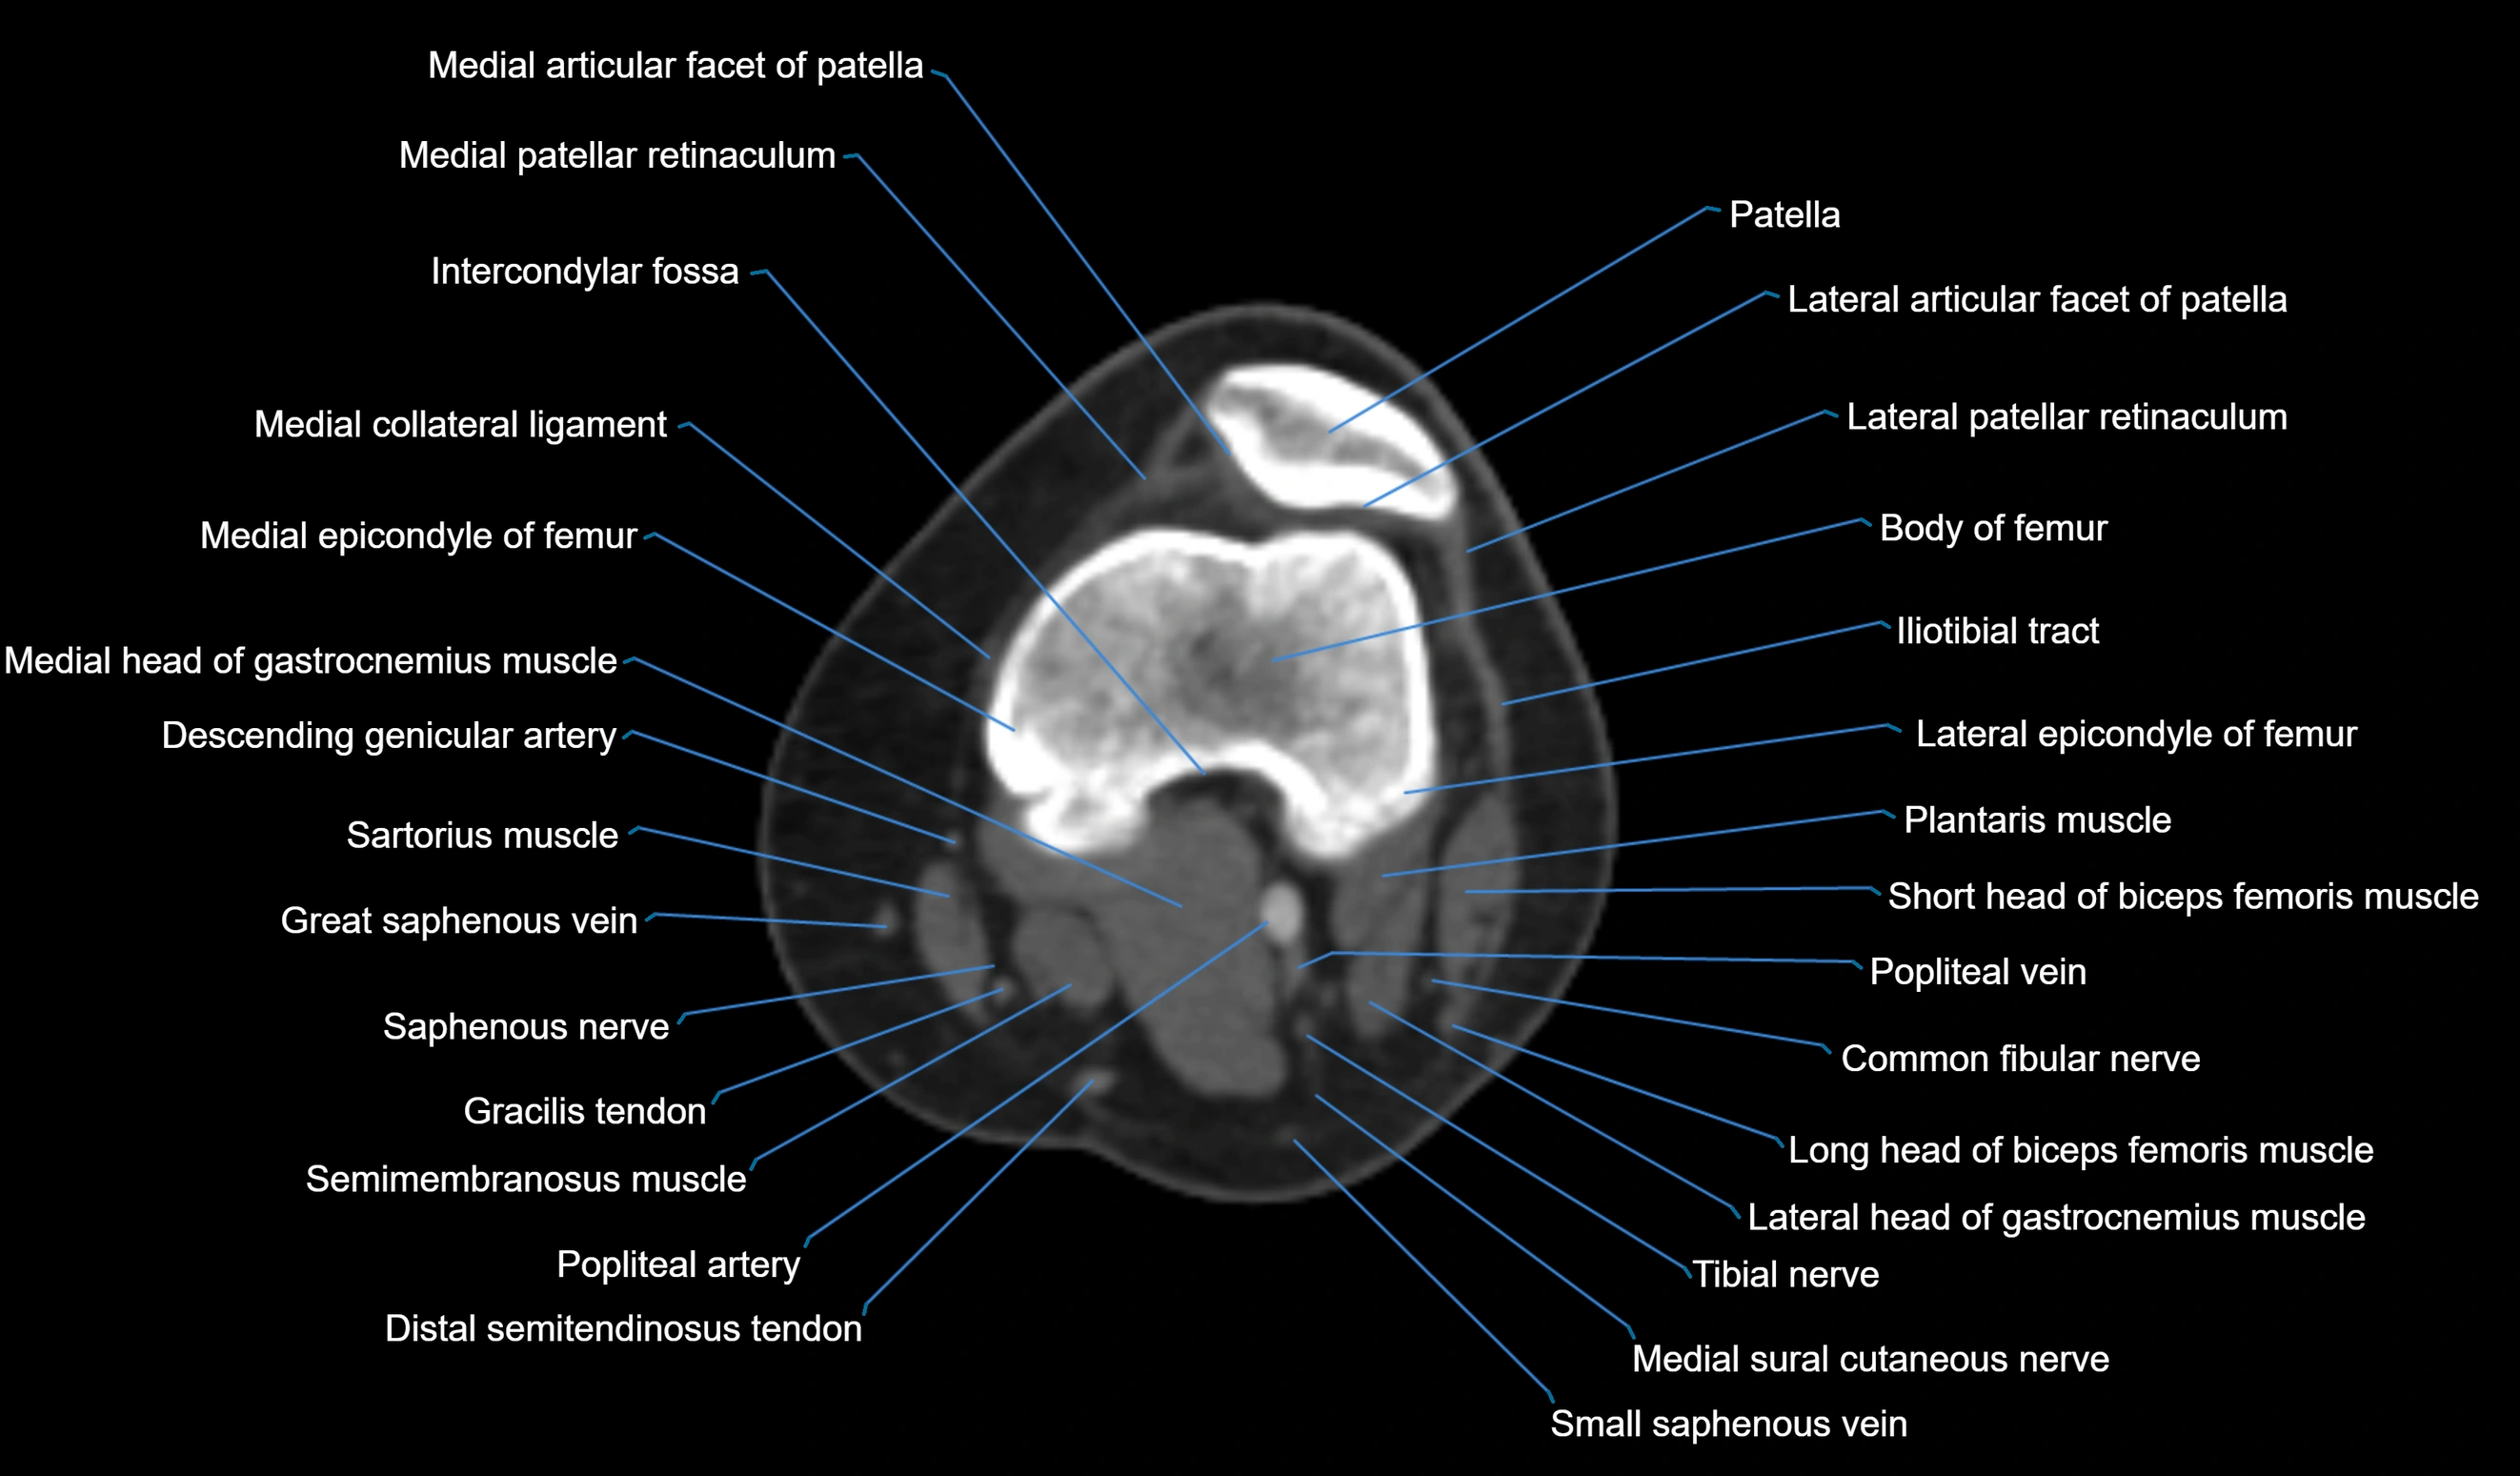

- Patella

- Medial articular facet of patella

- Lateral articular facet of patella

- Medial patellar retinaculum

- Lateral patellar retinaculum

- Intercondylar fossa

- Medial collateral ligament

- Medial epicondyle of femur

- Lateral epicondyle of femur

- Medial head of gastrocnemius muscle

- Lateral head of gastrocnemius muscle

- Descending genicular artery (Articular branches)

- Sartorius muscle

- great saphenous vein

- Saphenous nerve

- Gracilis tendon (Distal)

- Semimembranosus muscle

- Popliteal artery

- Distal semitendinosus tendon

- Popliteal vein

- Common fibular nerve

- Medial sural cutaneous nerve

- Small saphenous vein

- Plantaris muscle

- Biceps femoris muscle (Short head)

- Biceps femoris muscle (Long head)